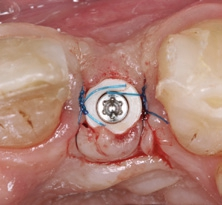

Mit der PEEK-Abdeckkappe, die über einen Klickmechanismus in die Innenkonfiguration des Implantats gesteckt wird, wurde das Implantat verschlossen. Die Abbildung 10 zeigt die optimale prothetisch orientierte Platzierung des Implantats für die Rekonstruktion mit einer direkt verschraubten Hybridabutmentkrone. Von okklusal ist das ausgeprägte bukkale Knochendefizit deutlich zu sehen. Mit einem Gemisch aus autologen Knochenspänen, die während des Bohrvorgangs implantatnah gewonnen worden waren, und Bio-Oss Collagen (Geistlich) wurde der Defekt aufgebaut. Aufgrund ihrer osteogenetischen, -induktiven und -konduktiven Eigenschaften ist der Einsatz von autologen Knochenspänen in der GBR in unserer Praxis Standard. Eine resorbierbare Membran mit verlängerter Barrierefunktion (Memlok BioHorizons) wurde nach Ablösung des Periosts, dem biologischen Konzept folgend, zur Abdeckung des volumengebenden Augmentats in direktem Kontakt zur angrenzenden Knochenoberfläche eingebracht (Abb. 11) [17, 18]. Resorbierbare Kollagenmembranen zeichnen sich dadurch aus, dass der Heilungsprozess der Weichgewebe auch bei Exposition der Membran weiter voranschreitet. Ein Kollagenkegel (Parasorb, Resorba) wurde zum Verschluss des gingivalen Defektbereichs eingesetzt, bevor das Weichgewebe spannungsfrei vernäht (Prolene 5-0, Ethicon) und ein postoperatives Röntgenkontrollbild gemacht wurde (Abb. 12–14). Die temporäre Versorgung erfolgte durch eine Kunststoff-Klebebrücke.